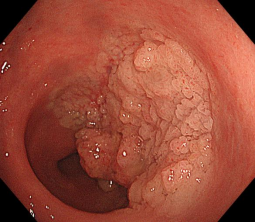

消化道早癌的病例展示(经内镜手术或活检证实):

胃窦印戒细胞癌

十二指肠降段早癌

直肠巨大侧向发育型肿瘤,内镜下完整切除(ESD),术后病理证实粘膜内癌,不需追加治疗,达到治愈目的,保留正常器官,避免外科手术。